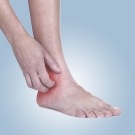

A Warm, Tender, and Erythematous Medial Ankle Rash

Jessica M. Ruiz-Myara, MS, OMS-IV; Hunter A. Vásquez, MS, OMS-IV; Joy Ishii Zarandy, DO, FAAFP, DABFM

A woman in her 50s presented to her primary care physician with a painful rash of her medial right ankle for the past 1 to 2 days.